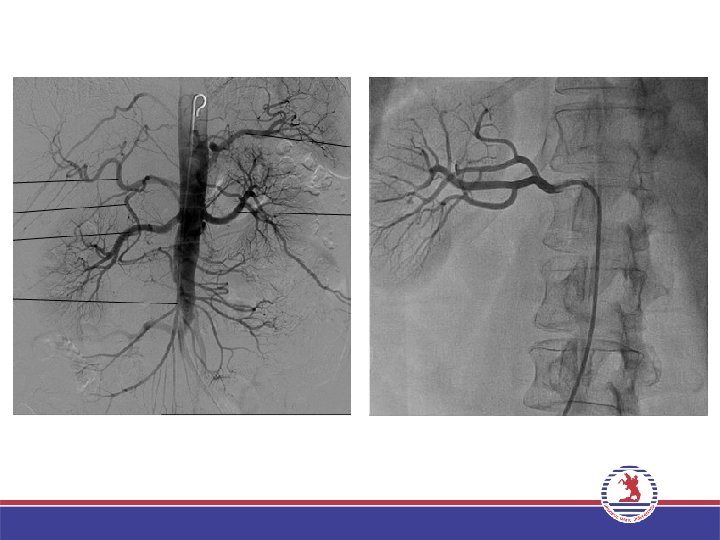

PERİFERİK ANJİYOGRAFİ • • Üst ve alt ekstremite arterleri Hepatik arter Splenik arter Mezenterik arterler Renal arter Bronşial arter Aortik dallar

PERİFERİK ANJİYOGRAFİ Yine Seldinger yöntemi kullanılarak periferik arteriyel yapıların (üst ektremite, alt ekstremite, renal, mezenterik vs. ) kontrast madde enjeksiyonu ile görüntülenmesidir. Temel anjiyografi tekniği (kateter yöntemi) ile yapılır. Endikasyonlar – – Damar darlıkları/tıkanıklıkları Travmatik damar yaralanmaları Arteriyovenöz fistül Vasküler malformasyonlar Arteriyovenöz malformasyon – Tümör kanlanması